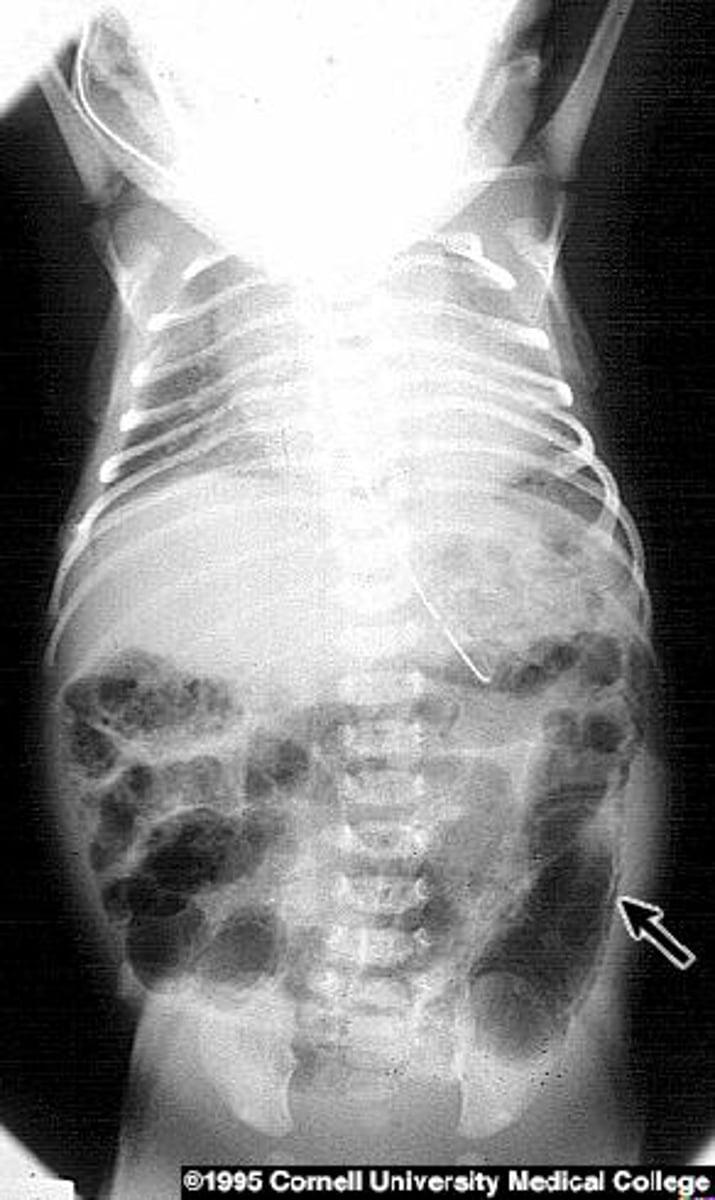

Necrotizing enterocolitis

- What do you see on X-ray? pneumocystis intestinal (air in bowel wall)

- Treatment? NPO, TPN (if nec), antibiotics and resection of necrotic bowel

- Risk factors? Premature gut, introduction of feeds, formula.

A 5 day old former 33 weeker develops bloody diarrhea

- What do you see on xray?

- Treatment?

- Risk factors?